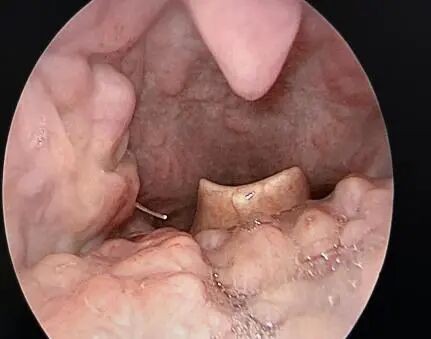

主诊医生耳鼻咽喉头颈外科副主任医师陈代波获知情况后,当即决定对李大哥实施手术。术中,医生首先经口食道镜检查,发现李大哥食管侧壁穿孔,但食道内未见鱼刺,又通过食管镜异物钳在食管破口处探查,仍未触及异物。遂考虑食管异物已经刺破食管到颈侧,立即进行颈侧切开,果然,鱼刺被发现。

彼时,鱼刺尖端已刺到颈动脉鞘,头段在食管壁内。凭借丰富的临床经验,医生完整取出长3cm像针一样的鱼刺。缝合食管穿孔后,颈部皮肤采用美容缝合,术后和自身皮纹一样。